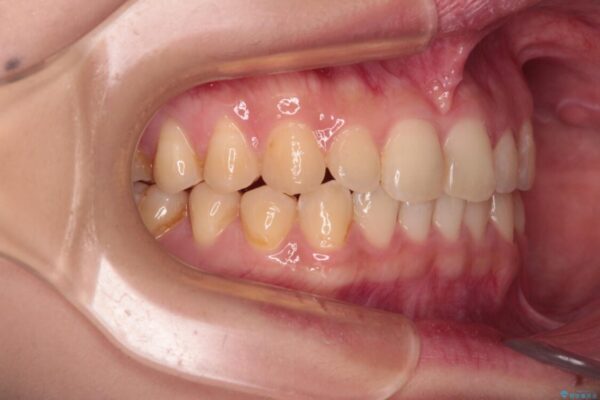

治療途中

• 治療途中の奥歯と矯正治療の後戻り インビザライン・ライトによる矯正治療 治療途中画像

クラウンはよりよい咬み合わせで装着したいため、インビザラインを1セット使用して概ね歯列を整えた時点で補綴治療を行い、その後仕上げの矯正治療を行いました。